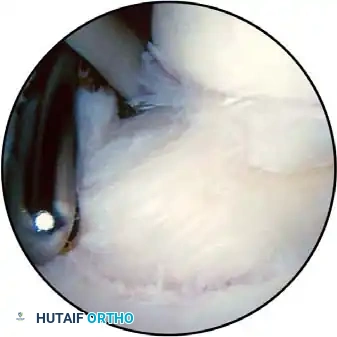

Once diagnostic evaluation is complete and hemostasis is secured, the therapeutic phase commences. Whether performing a SLAP repair, a Bankart stabilization, or a rotator cuff repair, the principles of tissue mobilization, anatomical footprint restoration, and secure biomechanical fixation remain paramount.

Modern arthroscopy relies heavily on suture anchors (biocomposite or all-suture constructs) and advanced arthroscopic knot-tying or knotless techniques. The ability to pass sutures through retracted, fibrotic tissue and secure them under appropriate tension without strangulating the microvascular supply is the hallmark of a master arthroscopist.